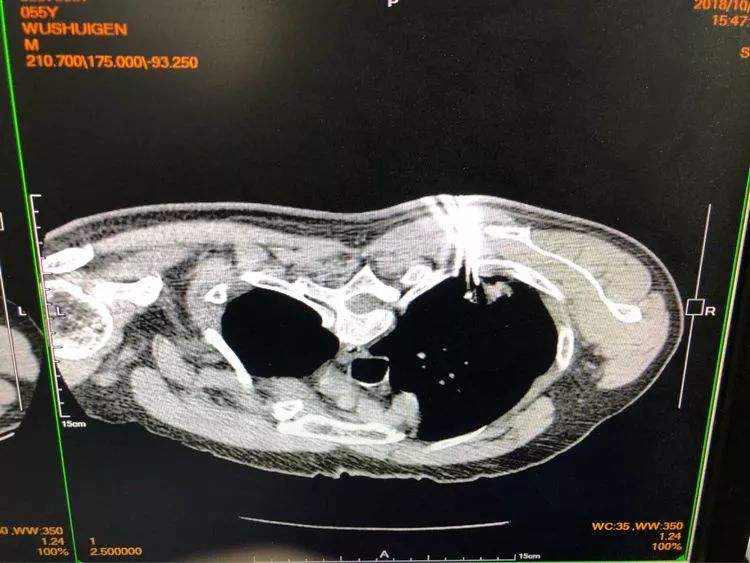

由于患者門診抗結核治療病灶稍增大,醫(yī)生們經(jīng)商議最終決定穿刺。雖然從影像看起來沒有穿刺路徑,不過沒關系,省胸科醫(yī)院經(jīng)驗豐富的內(nèi)科醫(yī)生們可以通過體位來調整。

待病理報告出來后告訴我們,結核是存在的,同時見不典型增生。

注意了,見不典型增生,就是癌前病變,但目前還不是癌,此時正是最佳手術時機,是可以治愈的!如果再晚一些時間,也許就沒機會了!